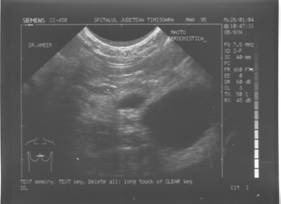

TUMORI BENIGNE

Tumorile si pseudotumorile sanului sunt patologii frecvente, dominate mai ales de fibroadenom, care este o patologie obisnuita la femeie tanara.